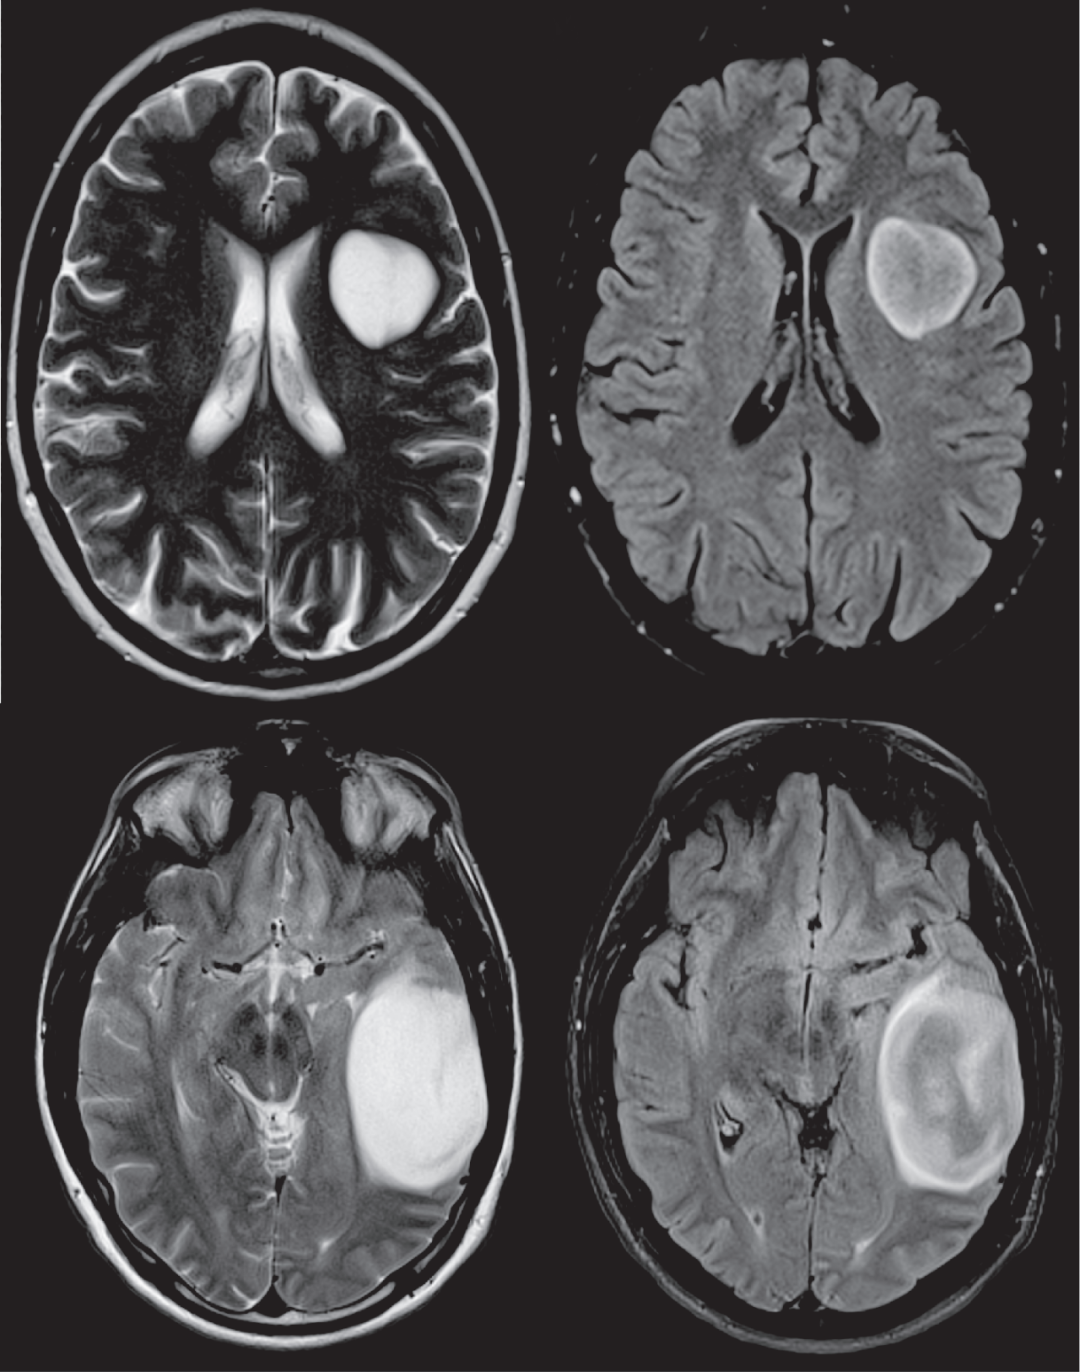

严格的排除标准:1)坏死腔不是 T2-FLAIR 错配;2)小囊肿不满足 T2- FLAIR 错配标准。不应将 T2WI 高信号的瘤内区域和 FLAIR 上相应的低信号(如瘤内囊肿或坏死核心)与 T2-FLAIR 不匹配体征的标准相混淆

T2WI 看似整体均质高信号,但是 FLAIR 出现明显的低信号(坏死/囊肿),未见强化,不符合 T2-FLAIR 错配。术后为少突胶质细胞瘤 IDH 突变型。

T2WI 看似整体均质高信号,但是 FLAIR 出现明显的低信号(坏死/囊肿),不符合 T2-FLAIR 错配。术后为少突胶质细胞瘤 IDH 突变型。